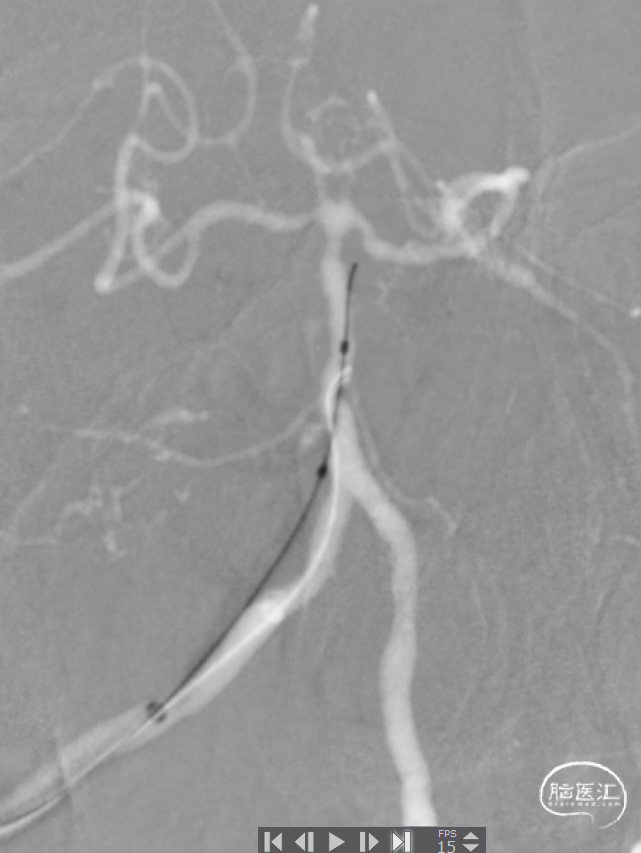

椎动脉后循环旋转造影

造影示:右侧优势椎,经右侧椎动脉导弯造影,双侧胚胎型大脑后动脉。

椎动脉V2、V3段迂曲,若不建立良好通路,则后续球囊支架无法到位释放。

基底动脉狭窄位于双侧AICA开口处,且无双侧PICA,其供血区由双侧AICA、SCA分支代偿供血。

6F 90cm 长鞘+5F 115cm 通桥银蛇®颅内支持导管建立通路。

0.014in*200cm 微导丝超选,球扩支架 2.5*8mm到位。

充盈球囊支架释放。